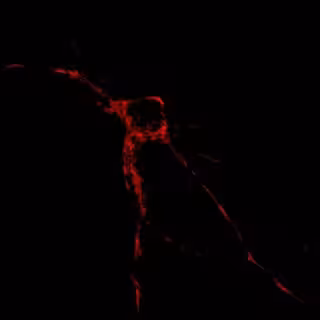

En Rojo, Localización De Mitocondrias En Una Neurona

Científicos del Instituto de Investigación Biomédica (IRB) de Barcelona han logrado identificar un grupo de seis genes cuya función es regular el movimiento y posición de las mitocondrias en las neuronas, un papel clave en el funcionamiento y viabilidad del cerebro.